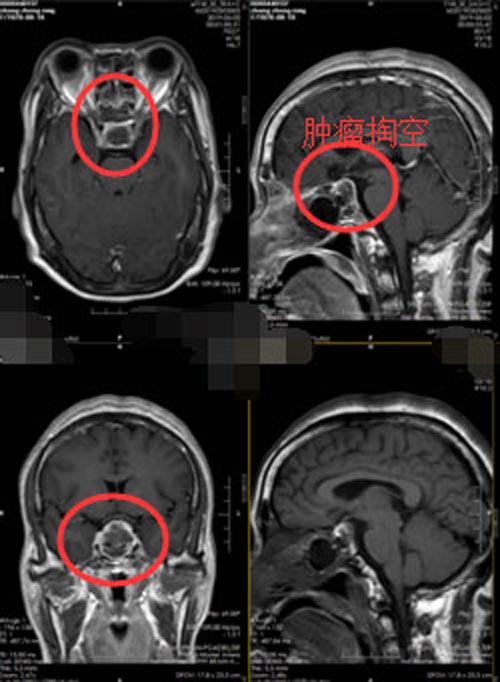

一个月前,一位亲戚来看她,竟然没有认出来张大姐,容貌变化这么大,让她和家人都无法理解。家人建议她去附近医院先看看,脑部核磁共振检查提示垂体大腺瘤,肿瘤已经是3.7cm×1.8cm×3.2cm。

完善相关的术前准备后,张大姐在内镜下“经鼻垂体瘤切除的微创手术”,手术过程顺利,出手术室时就已经苏醒,视力视野无异常。术后2天康复出院,生长激素由原来的243.40ug/L下降到正常范围的 4.63ug/L,她自己也感觉到四肢有明显的松解。

▲手术前